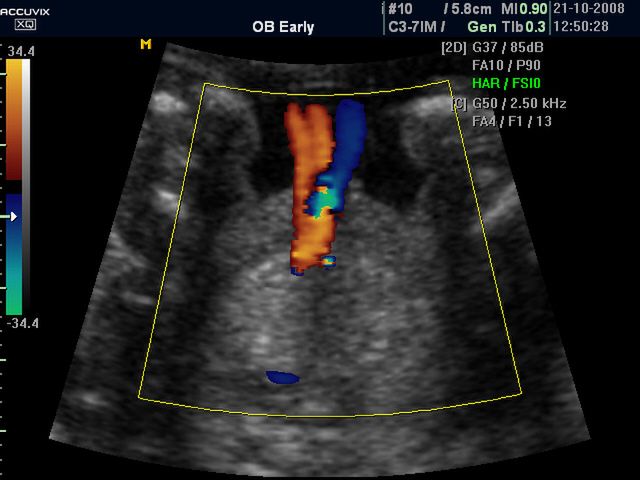

/ 10Zdjęcia płodu - pępowina w 29 tygodniu ciąży

Obraz

Płód w 29 tygodniu ciąży, na zdjęciu widoczne miejsce przyczepu pępowiny